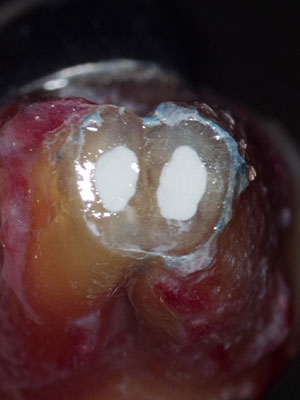

次の画像をご覧ください。歯の中にある黒い線が「根管」を示しています。

画像

根管の形は患者さんひとりひとりによって異なります。さらに、狭いところは、直径1mmもありません。こんなに狭くて複雑な根管から、細菌に感染した組織をきれいに取り除くというのは、どんなに難しい作業なのかお分かりいただけると思います。

当院では、歯科専用の顕微鏡「マイクロスコープ」や「高倍率ルーペ」で患部を見ながら治療します。特に、マイクロスコープは、患部を十数倍に拡大して見ることができます。狭くて複雑な根管内を処置するには、拡大視野による施術が欠かせません。

写真は、実際にマイクロスコープで見た患部の様子です。どれだけ精度の高い治療ができるか、おわかり頂けると思います。